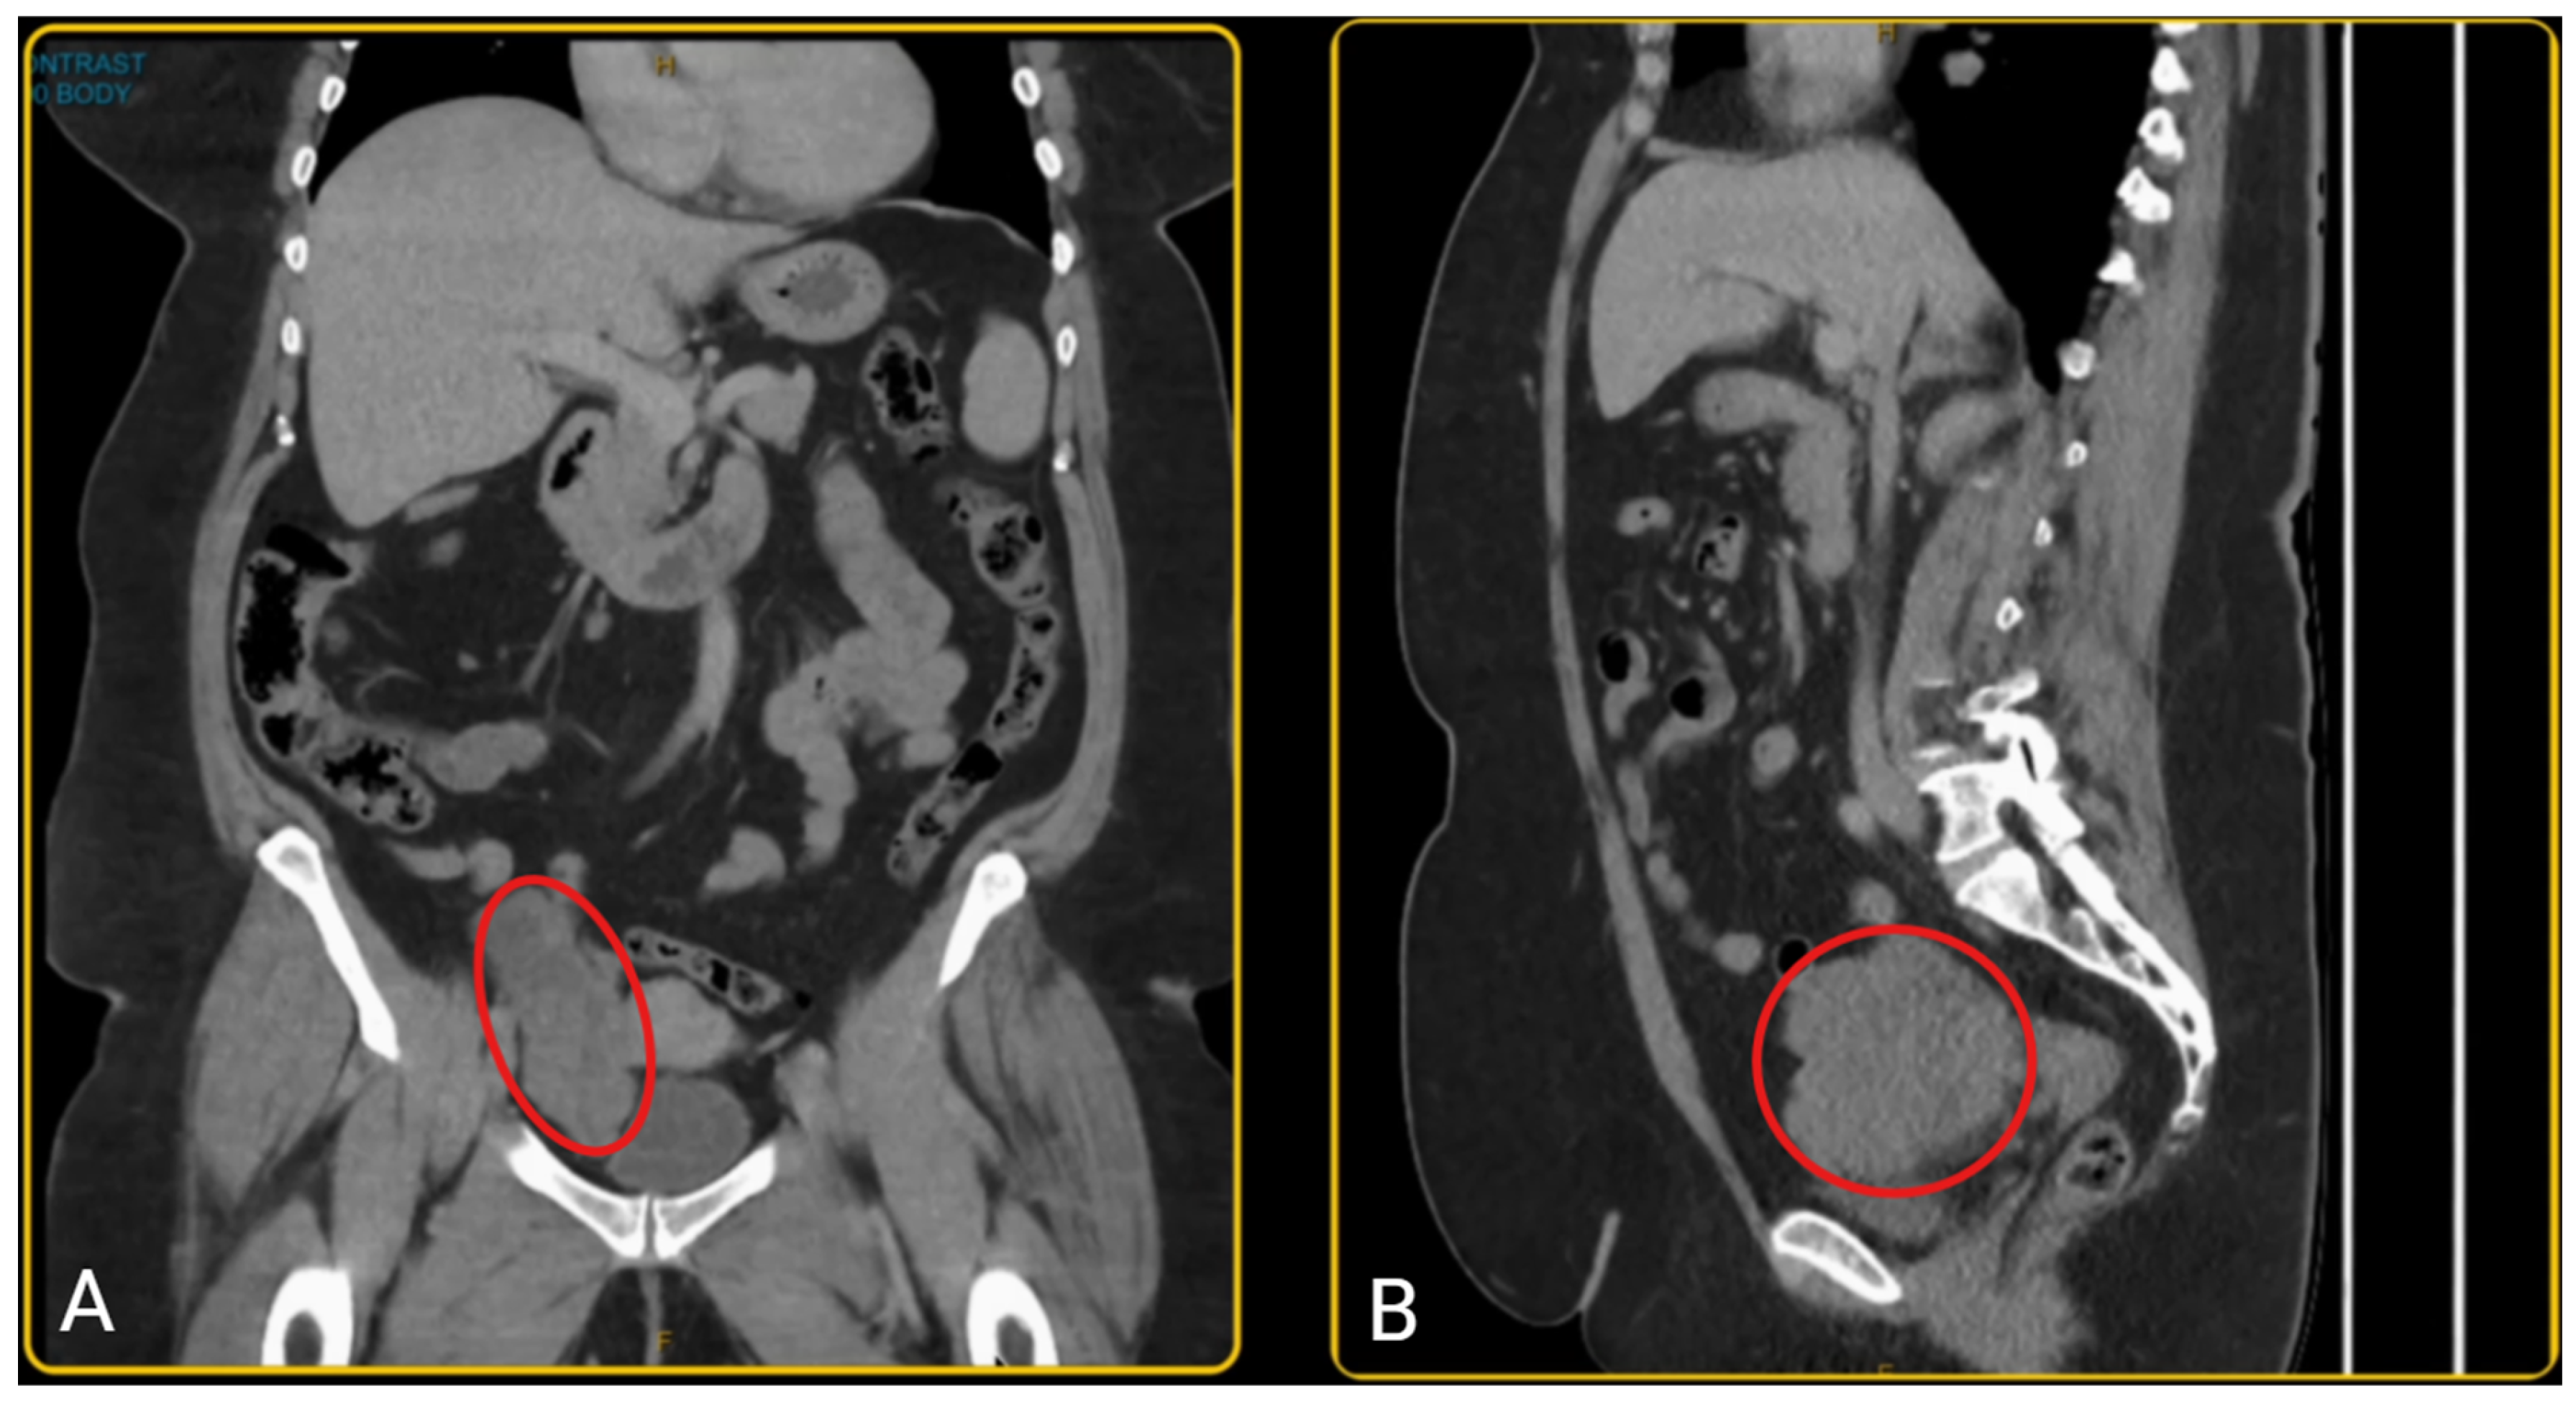

Amazon.co.jp: 子宮体癌・卵巣癌におけるStaging Laparotomy: en。改訂2版 子宮体癌・卵巣癌におけるStaging Laparotomy。Raising Awareness of Intraoperative Diagnostic Challenges to。中古品を購入し、自宅で裁断しました。裁断面は綺麗です。(写真2枚目)表紙カバーなどにヨレがあります。(写真3,4枚目)自宅で問題なくスキャンできました。ペット、喫煙なしです。※DVDなしです「子宮体癌・卵巣癌におけるStaging Laparotomy en bloc骨盤・傍大動脈リンパ節郭清術」田畑 務定価: ¥ 18000#田畑務 #田畑_務 #本 #自然/医療・薬学・健康。595_2020_2121_Fig1_HTML.png。小児歯科学クリニカルテキスト・ベーシックテキスト 第2版。【大型本】講談社 顎口腔外科診断治療大系。ゲノム 生命情報システムとしての理解。リンパ系局所解剖カラーアトラス